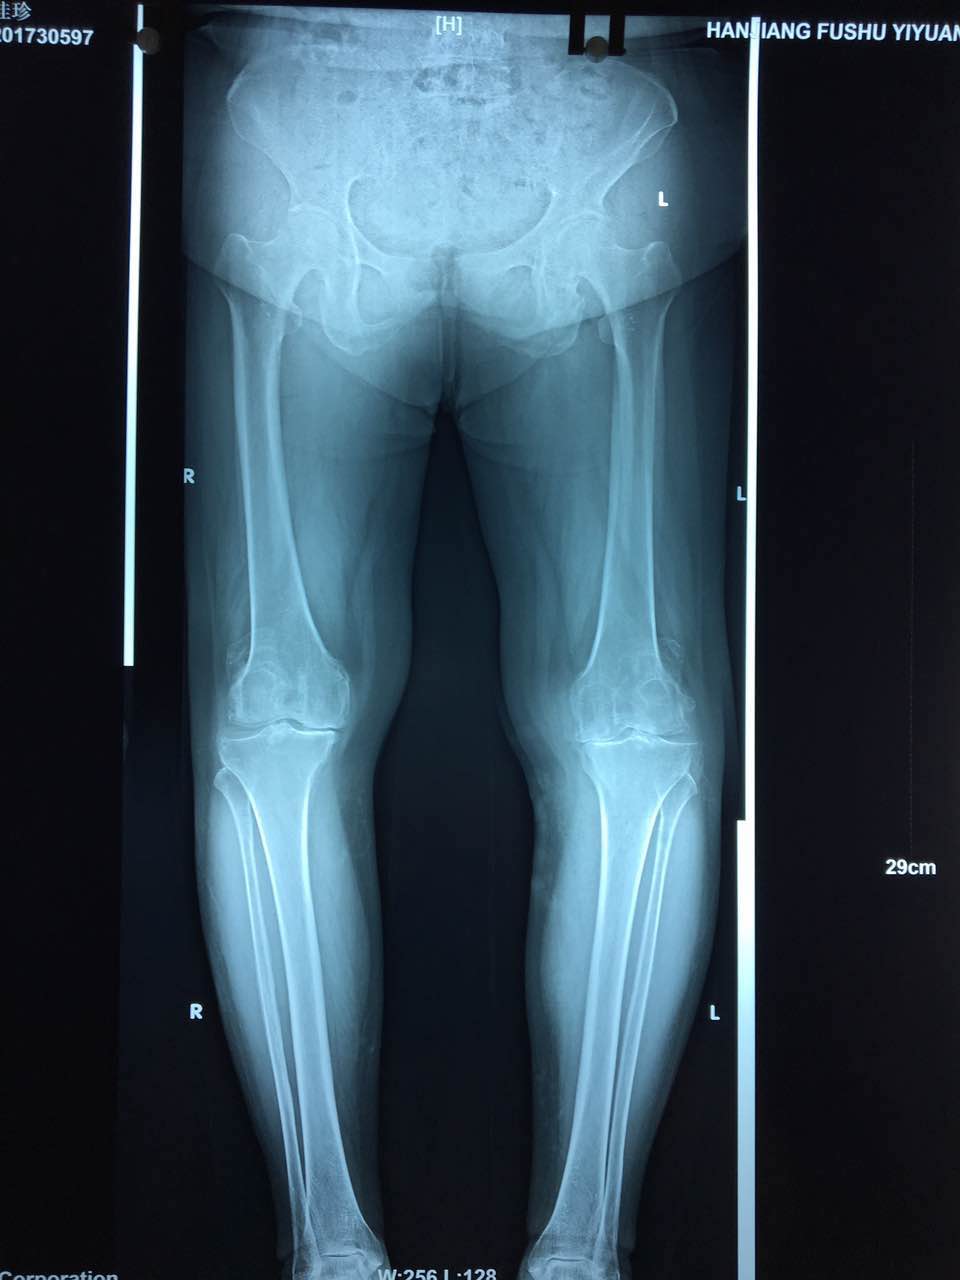

患者,师XX,女,68岁,农民,以“左侧膝关节疼痛伴活动受限7年,加重1月”之主诉收住院。7年来,左膝关节疼痛进行性加重,活动逐渐受限,反复保守治疗症状无缓解,因疼痛难忍,严重影响日常生活起居,行走困难,主动要求手术治疗。

患者术前影像资料